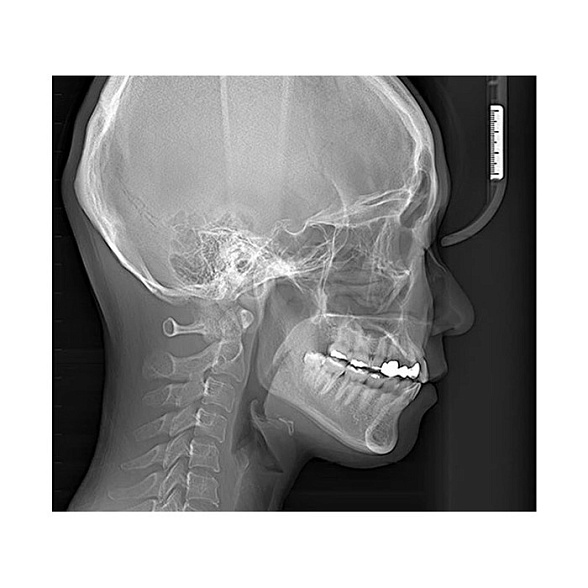

Цифровой дентальный томограф X-Radius Compact 3D — это современное решение для стоматологических клиник, стремящихся к повышению качества диагностики при разумных инвестициях. Аппарат сочетает в себе передовые технологии получения трехмерных изображений, надежность и эргономичный дизайн, что делает его идеальным выбором для широкого спектра задач: от имплантологии и эндодонтии до ортодонтии и хирургии.

Ключевой особенностью X-Radius Compact 3D является компактный размер FOV (поля обзора) 10х10 см. Этот формат оптимален для получения детализированных снимков одной или двух челюстей, области гайморовых пазух, височно-нижнечелюстных суставов. Он позволяет минимизировать дозу облучения для пациента, обеспечивая при этом всю необходимую информацию для планирования лечения.

- Ортодонтия: Анализ положения зубов, оценка состояния корней, планирование лечения на брекет-системах или элайнерах.

Чем КЛКТ отличается от обычного панорамного снимка?

Ортопантомограмма (ОПТГ) — это двухмерное суммационное изображение всей челюсти, на котором структуры могут накладываться друг на друга. КЛКТ (3D-томограф) создает трехмерную объемную модель, позволяя врачу рассмотреть область интереса под любым углом, в любой плоскости без искажений и наложений, что кардинально повышает точность диагностики.